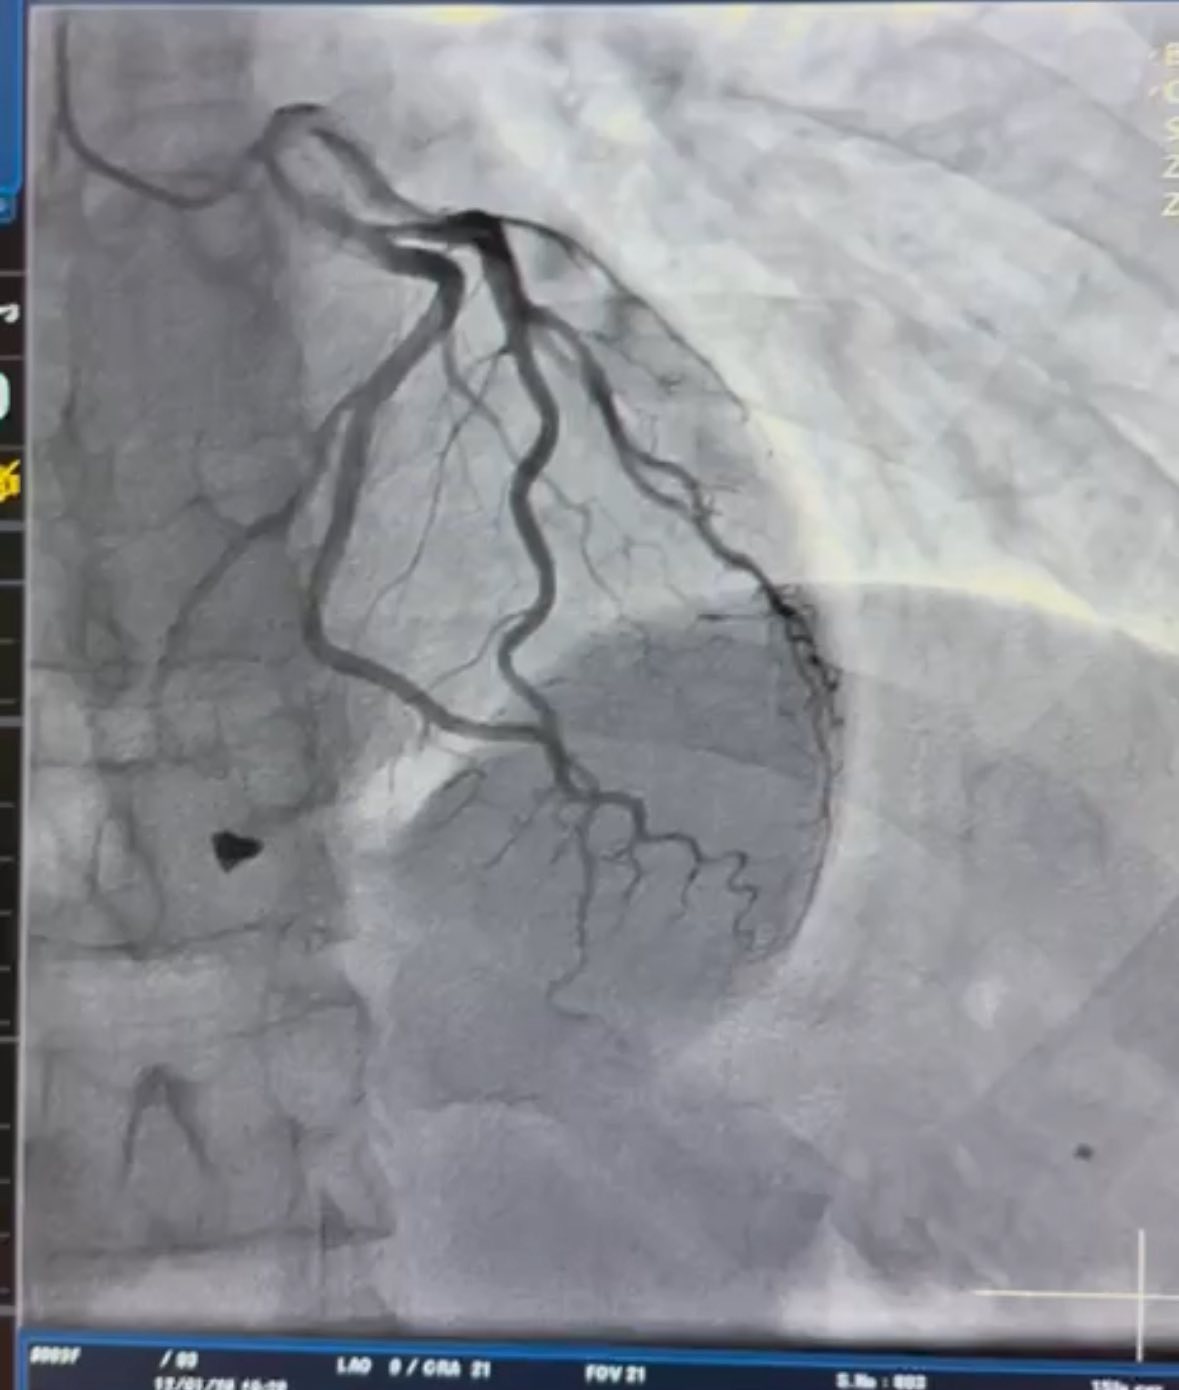

Після детального аналізу анатомії травми кардіохірургічна команда лікарні видалила вогнепальний осколок та виконала пластику тристулкового клапана, що дозволило відновити його функцію і забезпечити стабільну роботу серця.

Фото: Вінницька обласна клінічна лікарня імені М. І. Пирогова